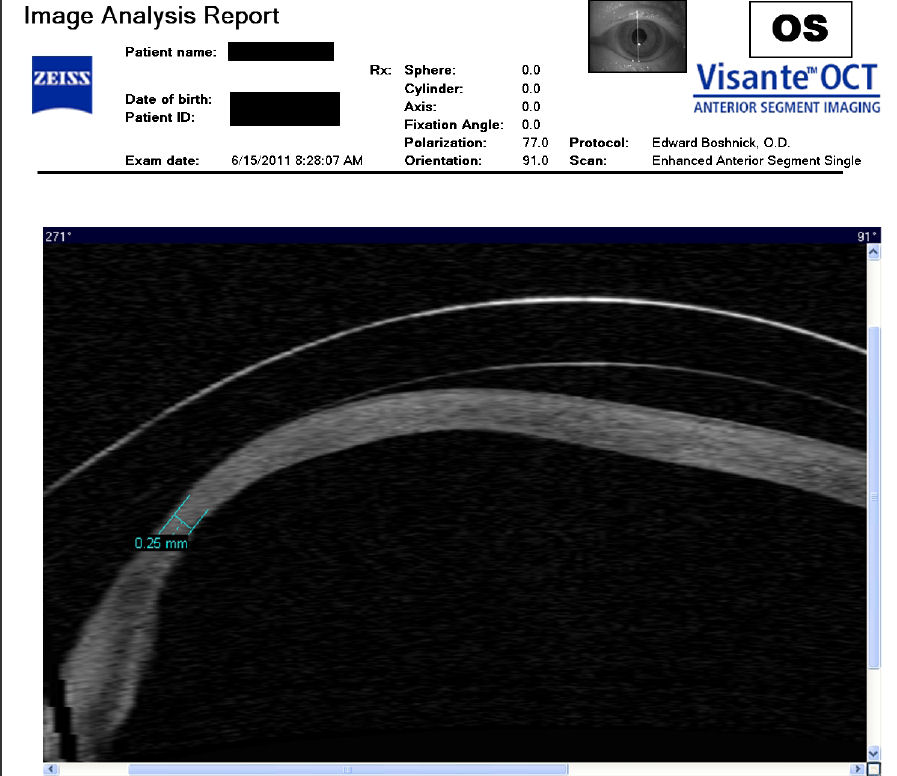

Следующие изображения были получены с использованием метода, называемого оптической когерентной томографией, или ОКТ. Прибор позволяет получить изображение в поперечном сечении путем сканирования передней части глаза (переднего сегмента) лучом света. Думайте об этом как об ультразвуке, использующем свет вместо звуковых волн для создания изображения живых тканей.

На снимке ниже показана роговица пациента, у которого после операции LASIK развилась эктазия. Пациент носит жесткие склеральные контактные линзы. Вы можете видеть выпячивание роговицы в самом слабом месте (эктазия), что приводит к сильному искажению зрения. Очки и мягкие контактные линзы неэффективны для таких глаз, как этот. Нажмите на изображение, чтобы увеличить.